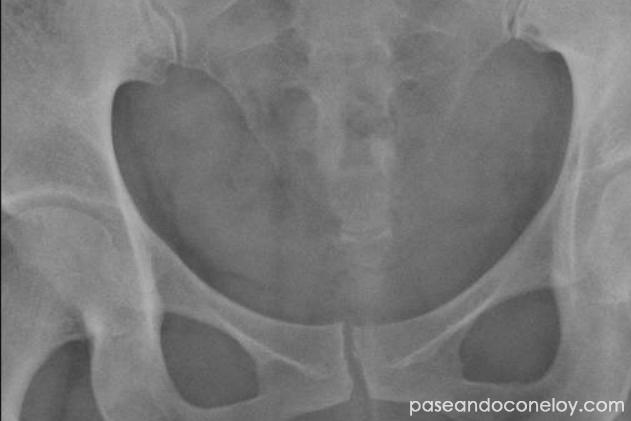

Algo que no me gustó en el momento que dije que me iba a tomar un tiempo es que me volvió a pedir la resonancia magnética (está en mi historial médico de la app del hospital), la volvió a ver y se fijó mejor que la primera vez. En ese momento vió que tenía inflamación en los ligamentos cercanos al coxis. Creo que es algo que se podría haber visto el primer día y haberlo atacado casi desde el principio, pero eso ya no importa.